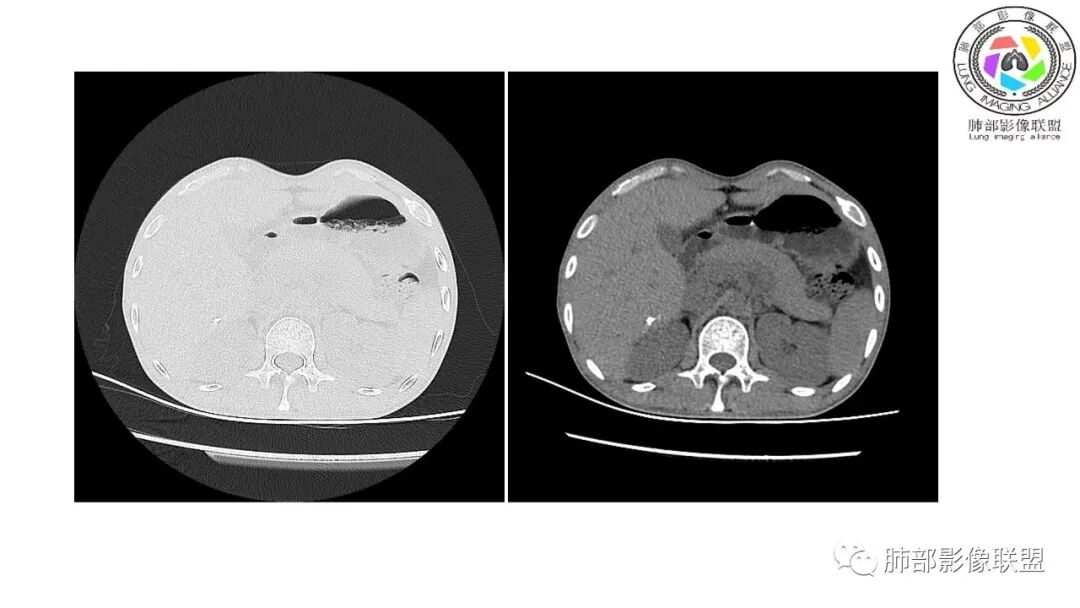

以下为2021-7-15日上腹部CT

影像与临床:1.青年男性,HlV阳性,颜面部皮疹(未提供皮疹图像)、发热(高热),实验室CRP、PCT高,T-Spot阴性。2.右肺下叶空洞结节,壁厚不均,边界清楚,其内线状影,未见液平及钙化,未见卫星灶,纵隔淋巴结增大,双侧腋窝见增大淋巴结。心腔内低密度提示贫血可能。肝脾影增大,未见结节影及块影。腹膜后见多发增大淋巴结。

综合分析:本例肺部影像学改变并不具有特征性,空洞性病灶须与多种疾病鉴别,但年轻HIV阳性患者,高热,皮疹,肝脾增大,纵隔、腋窝、腹膜后见多发增大淋巴结等都强烈提示马尔尼菲篮状菌感染的可能性。